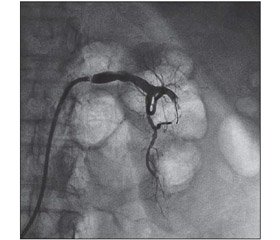

Для проведения ренографии и дальнейших манипуляций больные на несколько часов переводились в отделение кардиохирургии ДОКТМО. Катетеризация почечной артерии выполнялась через бедренную артерию, а при хронической инфраренальной окклюзии — через периферическую артерию (плечевую в локтевой ямке). Проводилась тромбоаспирация, селективный тромболизис (актилизе 100 мг), баллонная ангиопластика, стентирование почечной артерии (4). Для устранения повреждающего действия рентгенконтрастных средств на почечную паренхиму использовали ацетилцистеин, который вводили пациентам на протяжении последующих 1–2 суток. Непосредственно после проведения вмешательства выполнялась также гемодилюция: 0,9% NaCl 1,0 мл/кг/ч и ощелачивание плазмы 4,2% раствором соды-буфер 1 мл/кг/ч с учетом темпа восстановления диуреза. На рис. 1–4 представлены ренограммы больной П., 58 лет (7 суток анурии), которые демонстрируют восстановление кровотока после катетеризации левой почечной артерии и локального тромболизиса.